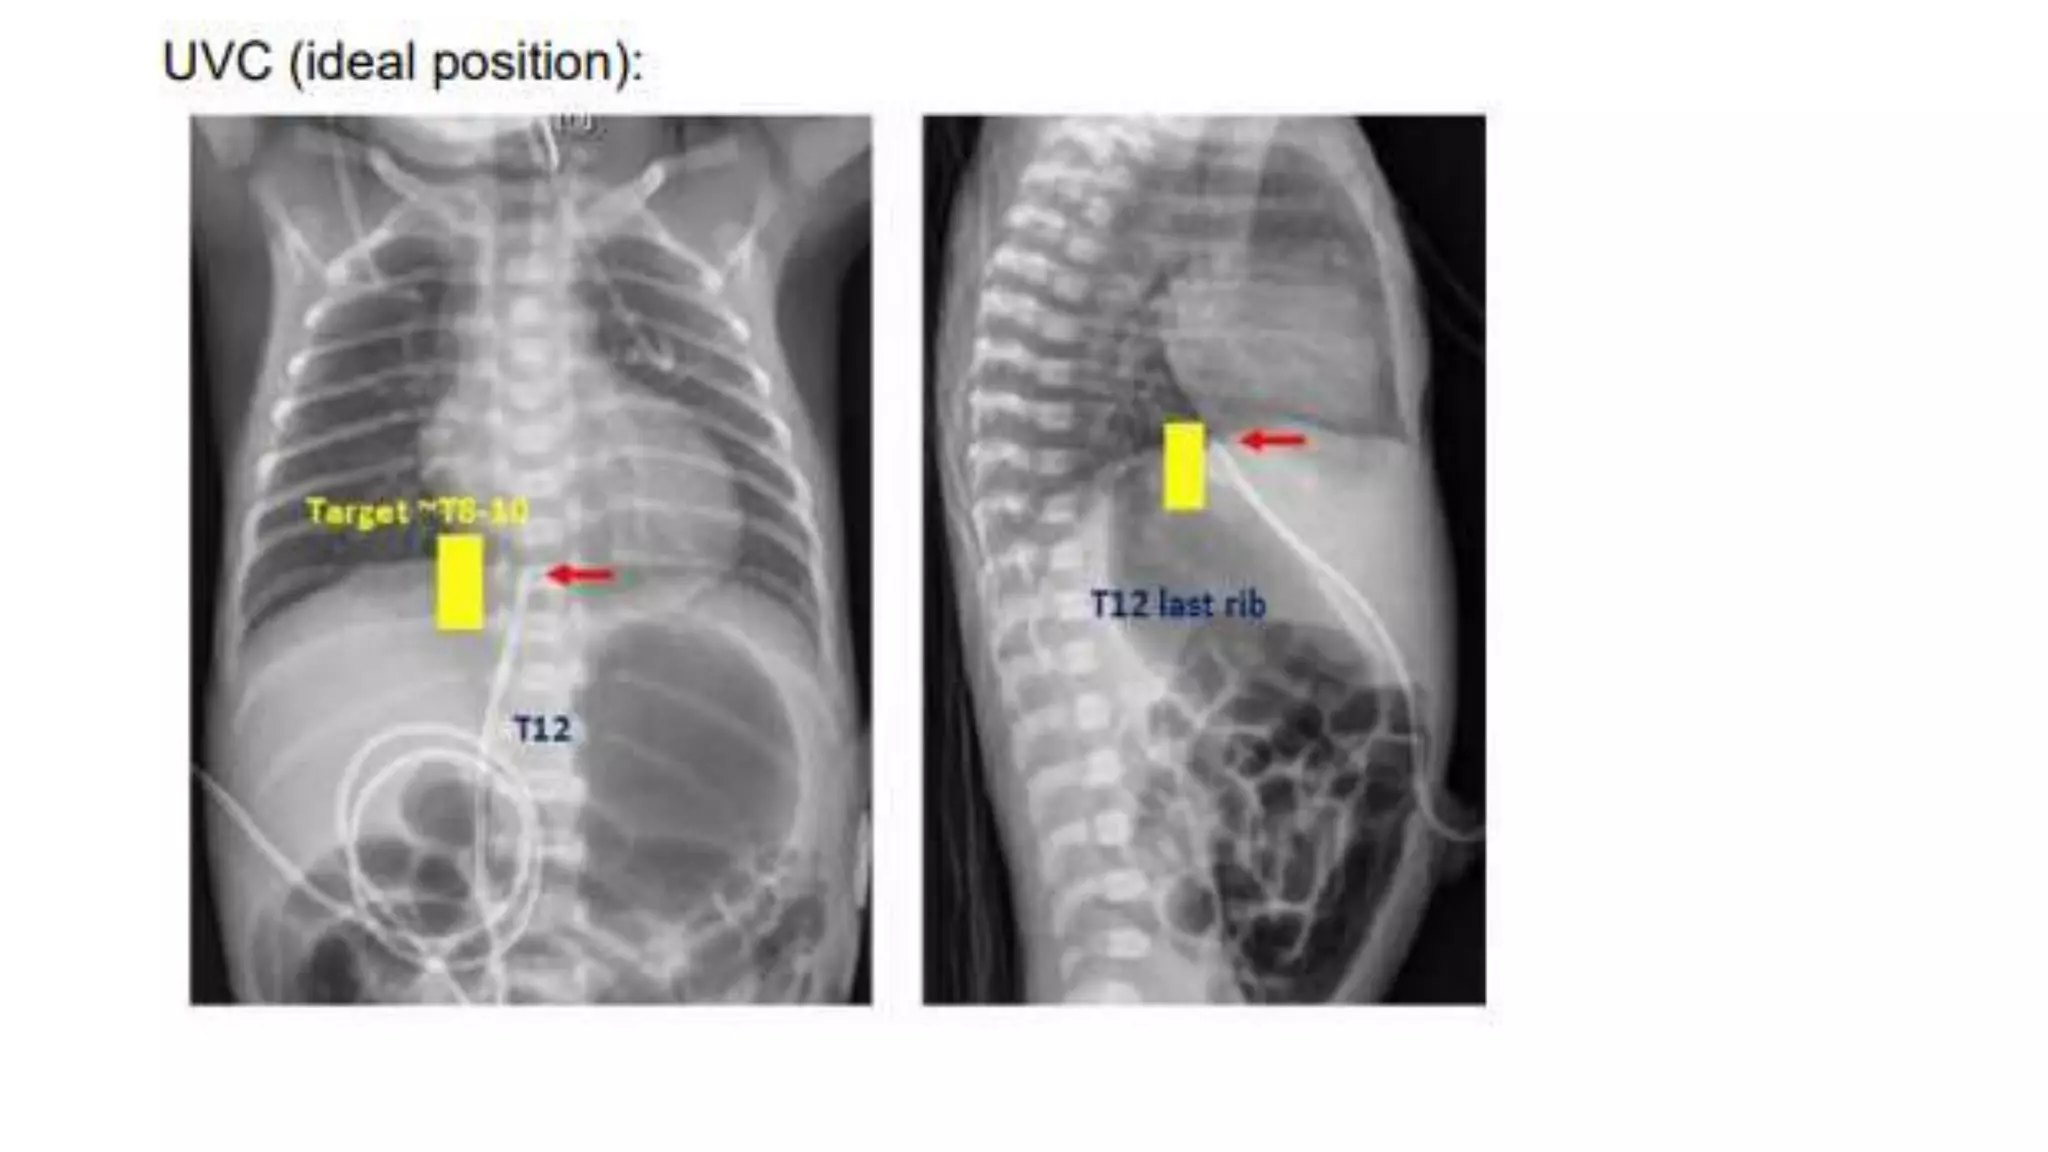

This document provides an overview of neonatal chest x-rays, including when they should and should not be performed, what a normal x-ray looks like, common positions of tubes and catheters, and common causes of respiratory distress in neonates. It discusses the appearance of a normal chest x-ray as well as conditions like respiratory distress syndrome, transient tachypnea of the newborn, meconium aspiration syndrome, and pneumonia. Surgical conditions like diaphragmatic hernia and esophageal atresia are also reviewed.